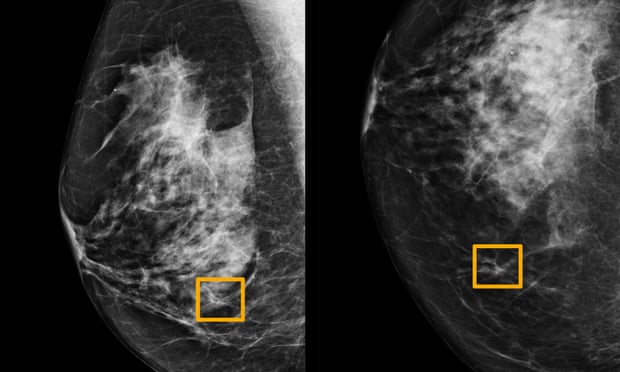

Хиймэл оюун ухаан хөхний хорт хавдрыг эмч нараас оновчтой илрүүлж байна

Шинжлэх ухааны Nature сэтгүүлд нийтэлснээр хиймэл оюун ухаан мэргэжлийн эмч нараас илүү хөхний хорт хавдрыг оновчтой илрүүлж байгаа ажээ. Google Health, Imperial College London-ы олон улсын судлаач эрдэмтдийн баг хэт авиан оношилгооны компьютер зохион бүтээж туршсан байна.

29,000 эмэгтэйн маммограмын зургийг туршилтад оруулахад хиймэл оюун ухаан зургаан мэргэжилтнээс бүрдсэн эмч нарын багаас илүү оновчтой онош илрүүлж байжээ. Мөн хоёр эмч зэрэг ажилласантай дүйцэхүйц амжилттай байгааг дурдсан байна. Учир нь хүнтэй харьцуулахад хиймэл оюун ухаан алгоритмын томъёоллоос бүрдсэн компьютер учир ядарч цуцна гэж үгүй юм.

Түүнчлэн эмч нартай харьцуулахад хиймэл оюун ухаан өвчтөний түүхийг судлаагүй зөвхөн хэт авиа оношилгооны зургаар онош тавина. Энэ нь цаг хугацаа хэмнэсэн, эмч нарын ажлыг хялбарчилсан арга юм. Хиймэл оюун ухаан эмч нартай харьцуулахад буруу оношлох магадлал 1,2 хувиар бага байжээ.